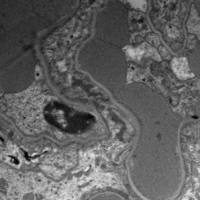

EVG染色样片参考:

弹性纤维呈蓝黑色;胶原纤维呈红色;背景呈淡黄色。